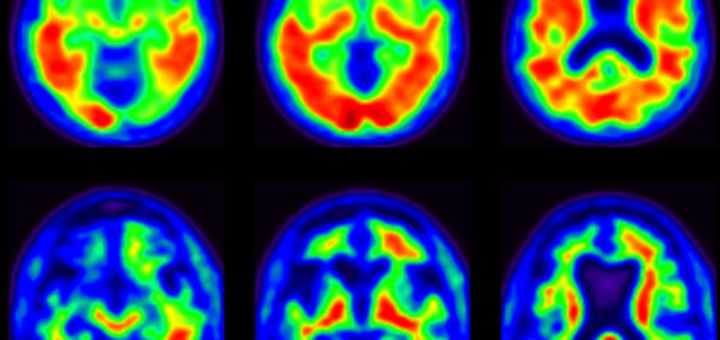

Dr. Kaci Fairchild is a licensed clinical psychologist whose research focuses on the non-pharmacological rehabilitation of late life cognitive impairment and neuropsychiatric disorders. She recently received the Alzheimer’s Association new investigator grant award which...